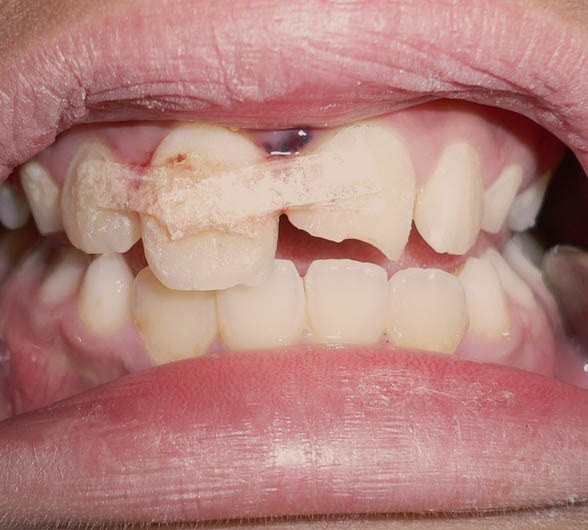

Fractured Front Teeth With Simple Splint